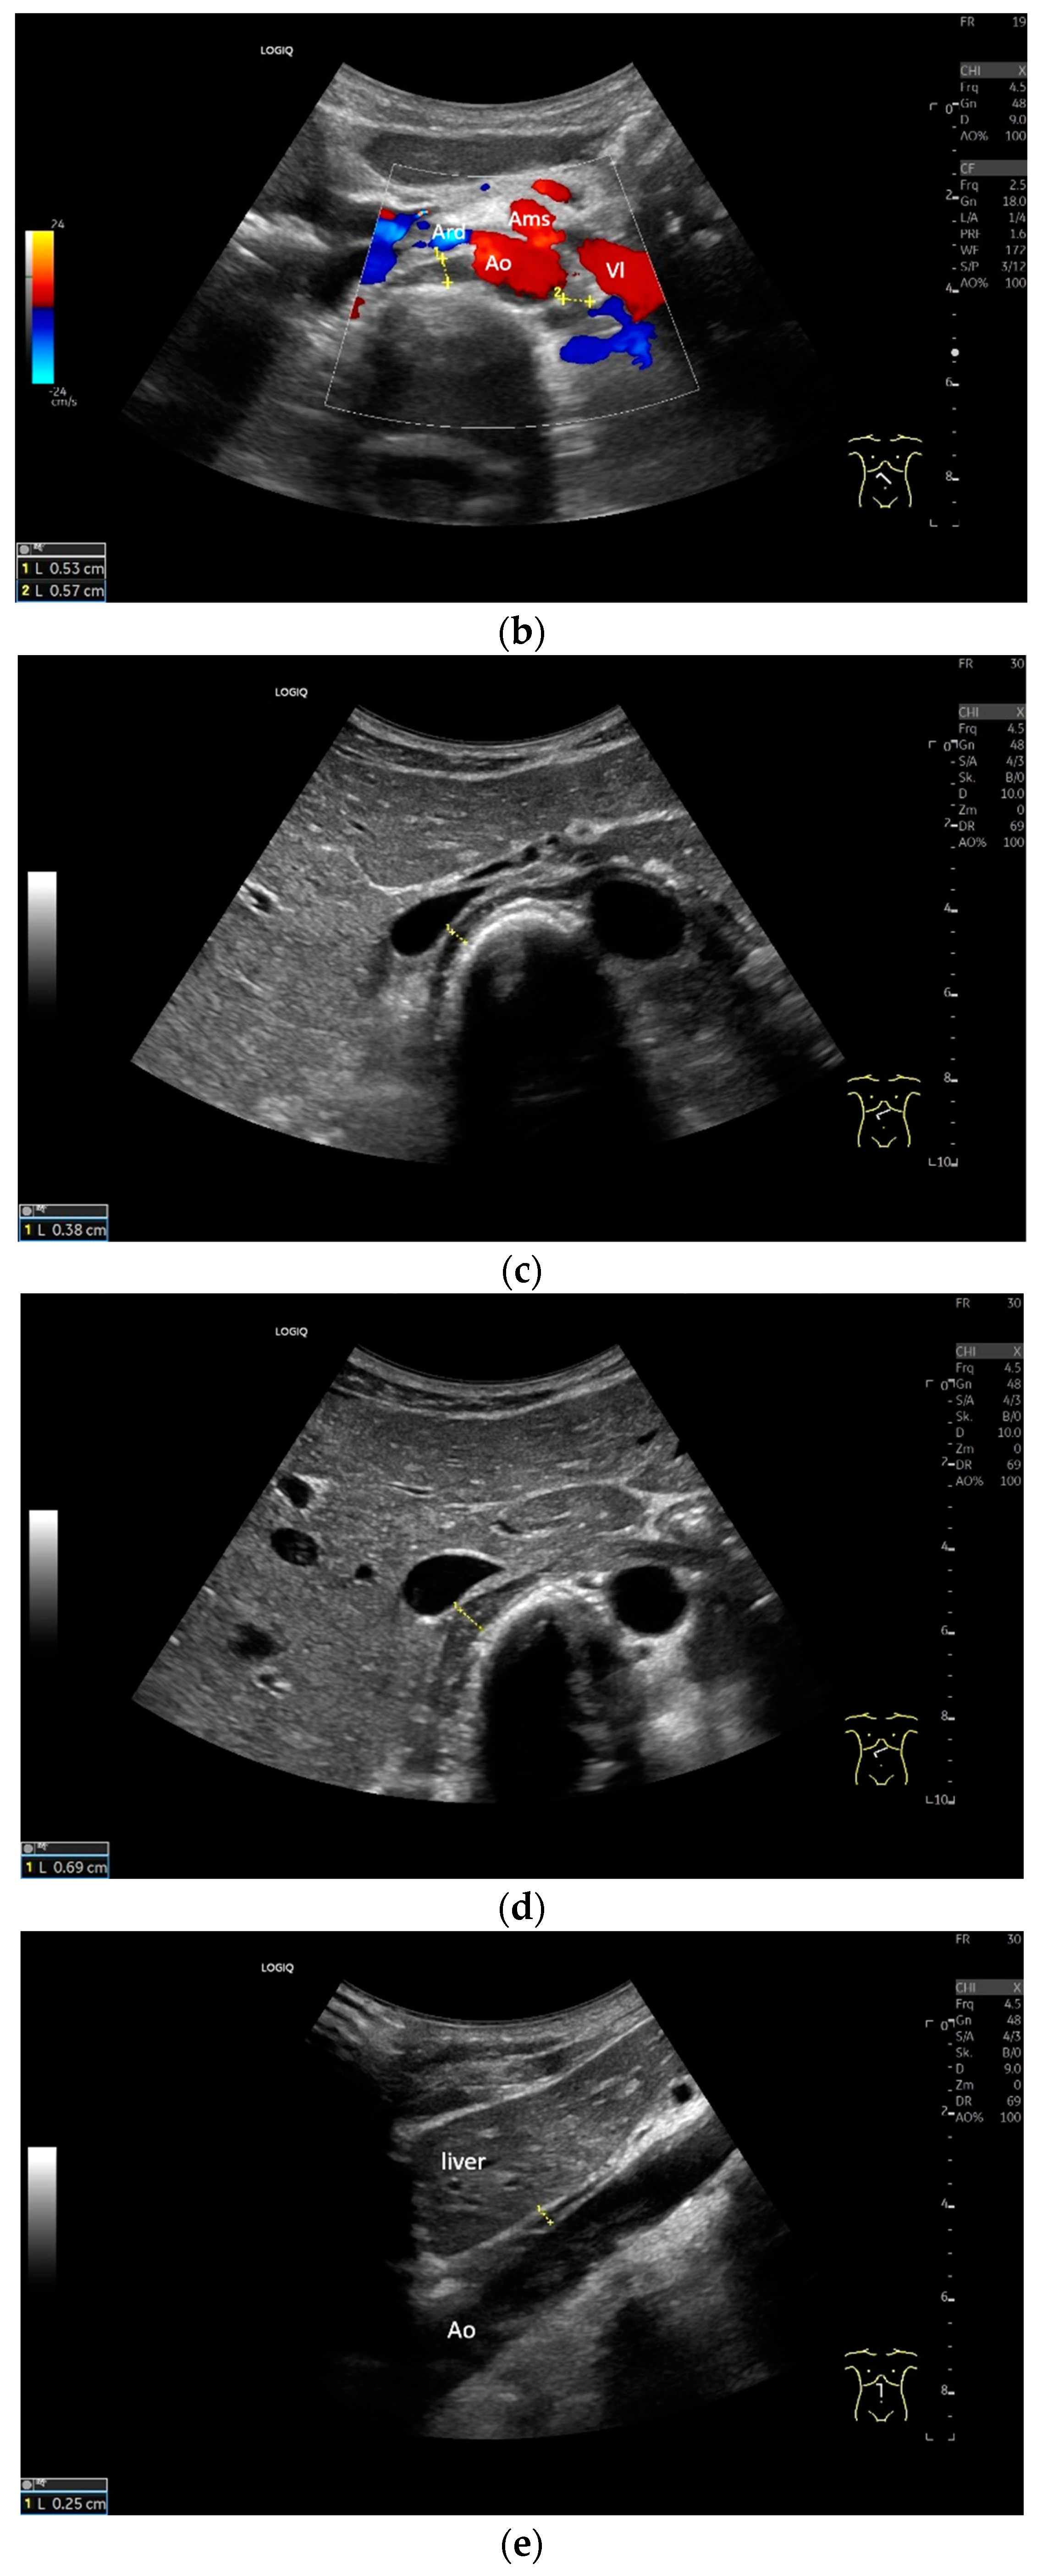

Lateral transducer position in the zone of apposition: The transducer is positioned longitudinally and laterally in the area of the mid-axillary line or slightly ventral to it between the anterior and mid-axillary lines, approximately in the 8th or 10th intercostal space. The diaphragmatic reflex is located on the inner side of the ribs below the pulmonary glide with pulmonary reverberations. This localization of origin of the diaphragm from the inner side of the rib cartilage is referred to as the zone of apposition (Figure 3). As this localization is only a few centimeters below the skin surface, high-resolution linear transducer use is highly recommended. In this position, the diameter of the diaphragm is measured during inspiration and expiration [2,3,4,5] (Figure 4). The thickness of the diaphragm varies, with caudal parts being thicker than cranial parts. The measurement of diaphragm thickness is highly variable depending on the intercostal space chosen, with thickness varying by up to 6 mm between the intercostal spaces [6]. It is therefore important to select the same position for comparable measurements and, if necessary, to mark the location for the transducer position [7]. Obesity limits assessment of the diaphragm [2].

To assess the diaphragm and its function, the diaphragm’s thickness, contraction and excursion are determined. Diaphragm thickness is mainly measured in the zone of apposition and excursion in the subcostal position. The diaphragm thickness is measured at end-expiratory (Tendexpir) and end-inspiratory (Tendinspir) points. Expiratory and inspiratory measurements should be taken with exactly the same transducer position. The measurement is taken at the outer edges of the hypoechoic muscle and at an angle of 90° to the diaphragm’s surface (Figure 4).